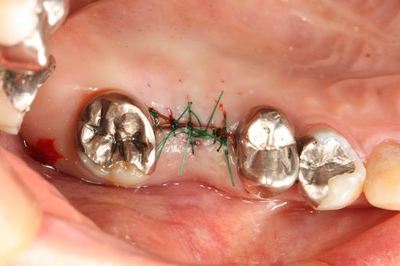

いよいよ本日のオペを行います。

ミラー像

前後の金属も今後除去していきます。

GCソフトレッチで縫合して終了です。